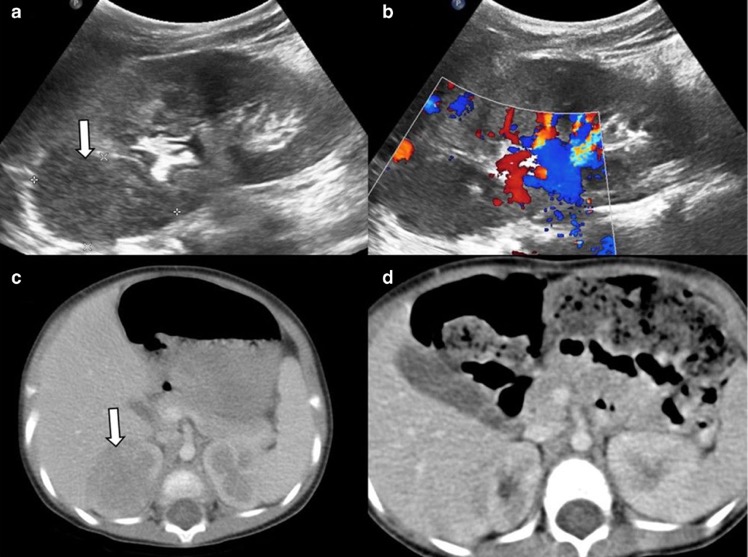

- Hématome sous-capsulaire spontané